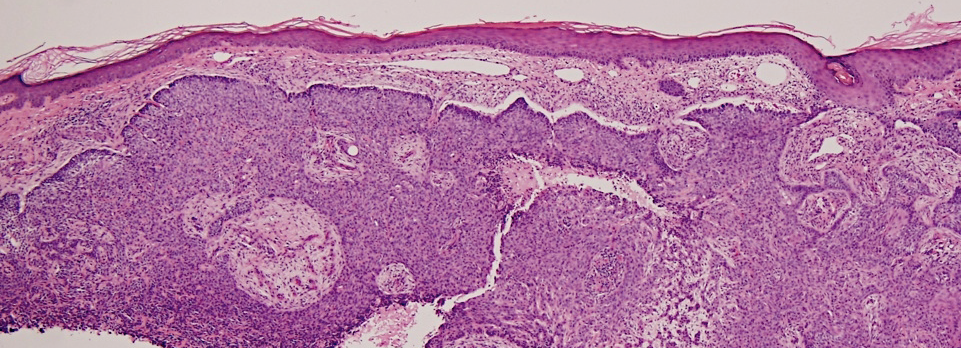

VA54: Left Superior Temple, Basal Cell Carcinoma, Nodular

- * denotes area of liquifactive necrosis with remnant necrotic cell debris